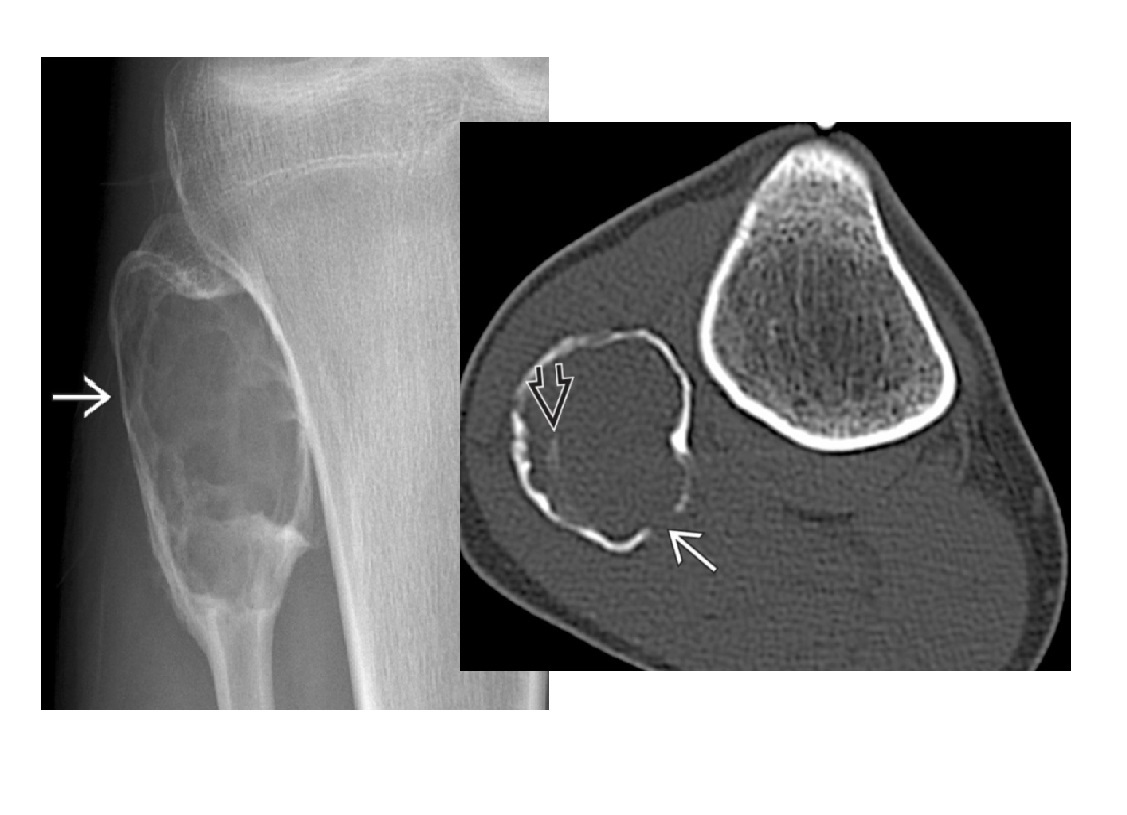

Chondrosarcoma

May be cecondary to

- Osteochondromas

- enchondromas

Chondrosarcomas occur in the pelvis, femur, humerus.

Skull base, TMJ

DDX

-Most well differentiated, low grade = ‘low grade chondroid lesion’ , cant differentate from enchondroma

-Bone infarct

MRI

Lobular growth

High 2 signal/STIR, low T1

ring and arcs/chondroid matrix islands on CT

Soft tissue extension

**endosteal scalloping. **

if no mineralized matrix/rings and arcs = aggressive/high grade

How to tell chondrosarcoma from enchondroma ?

* Pathological fracture occurring with minimal trauma

* Multilayered or spiculate periosteal reaction

* Permeative or moth-eaten osteolysis

* Cortical destruction

* A soft tissue mass

Endosteal scalloping more than 2/3 cortex